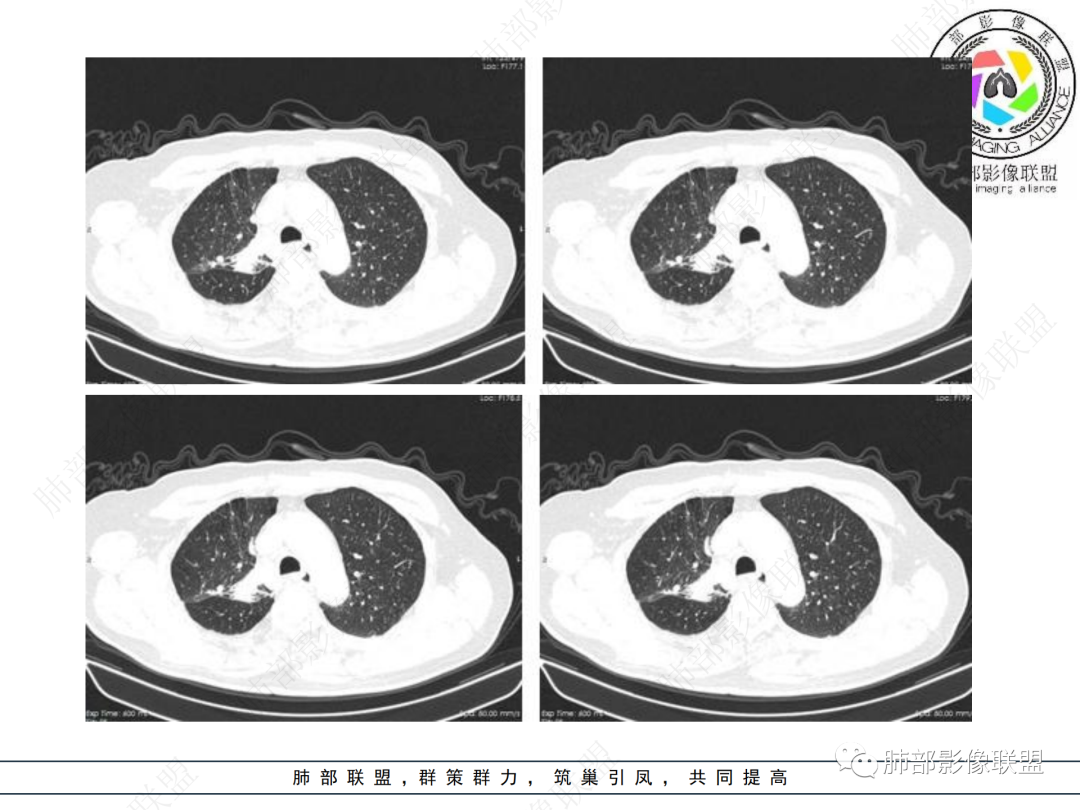

右肺上叶见不规则团块,边缘清晰,周围可见长索条及斑片影,胸膜顶增厚,右侧斜裂部分增厚,右上肺体积略缩小,增强后不均匀强化,考虑炎性肉芽肿性病变,结核?鉴别腺癌

右肺上叶体积变小,见不规则实性病灶,边缘有平直,长软毛刺,邻近胸膜明显增厚,叶间胸膜牵拉上提、局部凹陷;病灶周围不干净,可见长索条影;近端支气管壁略增厚。增强后增强不均匀,有低密度坏死,间隔较厚。考虑慢性炎性肉芽肿,结核可能,鉴别腺癌。

右侧胸廓变小,右肺上叶团块,边缘毛糙,长索条,周围斑点影,邻近胸膜增厚,气管不规整,密度不均,不均匀强化,考虑炎性肉芽肿,腺癌待排。

右肺上叶尖后段不规则斑块病灶,后缘以斜裂为界,有边缘平直,周围见纤维及多发小卫星灶,邻近胸膜反应性增厚,纵隔胸膜下少量积液,同时右肺中叶内侧段支气管扭曲及牵引性扩张,周边见爬行征,胸廊入口变窄,纵隔未见淋巴结肿大,综合上述慢性炎性肉芽肿,结核可能性大,支气管镜肺泡灌洗!

结合本病例,老年男性患者,慢性病程,急性加重,无吸烟史,影像学表现为右肺上叶尖后段斑片实变密度影,整体边界清晰,边缘平直收缩为主,周边散在纤维条索影,内部见支气管内粘液栓,血管影走形正常,没有明显破坏,增强扫描明显强化,缺乏典型分叶毛刺、胸膜改变,病灶也未显示清楚的磨玻璃勾边,病灶大而肺门纵隔未见肿大淋巴结,综合考虑慢性炎性肉芽肿可能性大。但恶性,结核能完全排除吗?我想对临床医生来说还是有很大考验的。